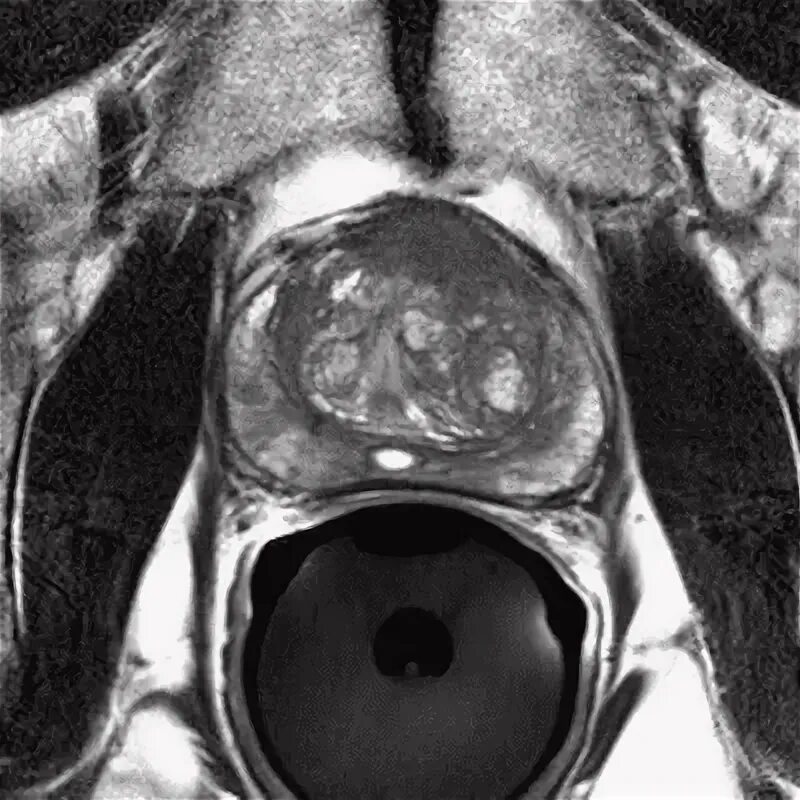

Ммрт